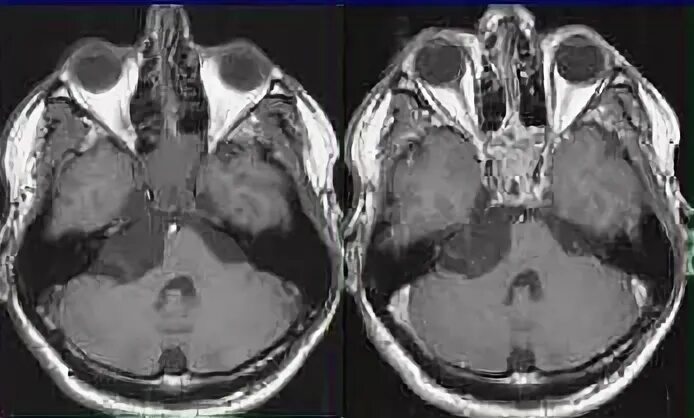

Мрт головного мозга мосто мозжечкового угла